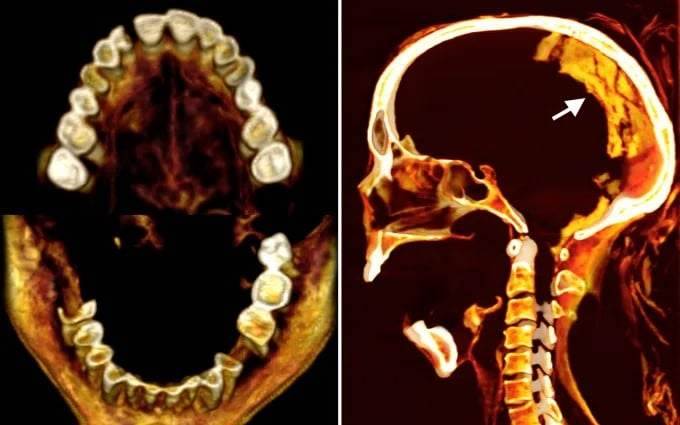

ولا يزال فريق آخر من العلماء مفتونين بـ "المرأة الصارخة" التي ماتت منذ حوالي 3500 عام، وقد استخدموا مؤخرًا عمليات مسح بالأشعة المقطعية للكشف عن تفاصيل حول مورفولوجيا المومياء وظروفها الصحية وحفظها، واستخدموا التصوير بالأشعة تحت الحمراء وتقنيات متقدمة أخرى "لتشريح البقايا افتراضيًا" وفهم ما قد يكون سبب تعبير وجهها المذهل.

وكشفت النتائج التي نشرت يوم الجمعة في مجلة "Frontiers in Medicine" أن المرأة كانت تبلغ من العمر 48 عامًا عندما توفيت، استنادًا إلى تحليل مفصل الحوض الذي يتغير مع تقدم العمر. وقد برزت جوانب معينة من العملية المستخدمة في تحنيطها.

ولم تجد سليم أيضًا أي شقوق في الجسم، وهو ما يتسق مع التقييم الذي تم إجراؤه أثناء الاكتشاف الأصلي، وهو أن المخ والحجاب الحاجز والقلب والرئتين والكبد والطحال والكلى والأمعاء لا تزال موجودة.

ووجد الباحثون أن طول المرأة المجهولة يبلغ 1.54 متراً، أو أكثر بقليل من 5 أقدام، وأنها كانت تعاني من التهاب مفاصل خفيف في العمود الفقري، وكشفت الفحوصات عن نتوءات عظمية على بعض الفقرات التي تشكل العمود الفقري. كما كانت عدة أسنان، ربما فقدت قبل الوفاة، مفقودة من فك المرأة.